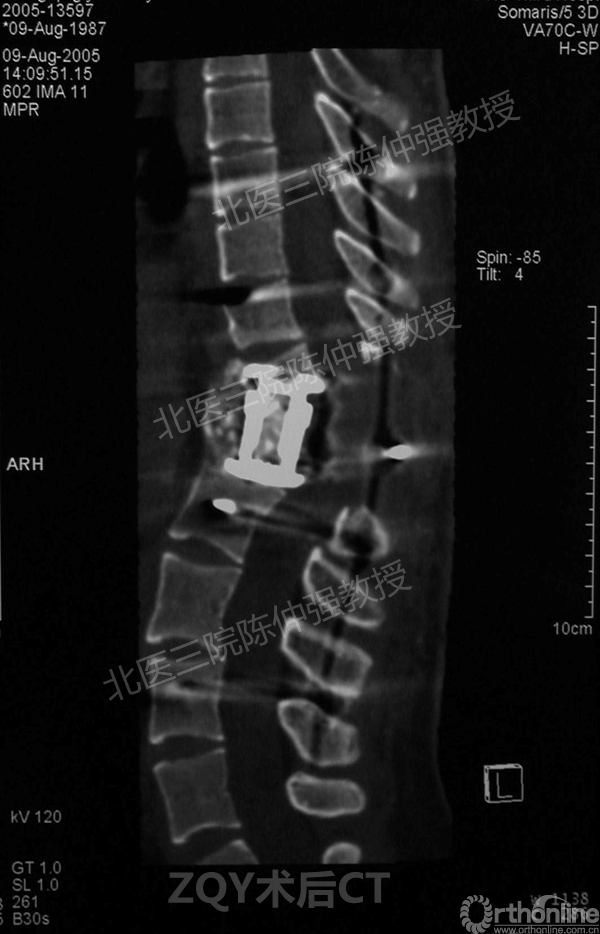

2005年,陈仲强教授在AOSpine年会上分享了一例胸腰椎陈旧结核性侧后凸畸形病例。资料如下:

ZQY术后

患者女性17岁,胸腰椎陈旧结核性侧后凸畸形,局部呈“麻花状”扭转,无神经功能受损表现。2005年,陈仲强教授带领团队实施后路+侧前方联合入路脊柱节段切除、双轴旋转矫形术。术后患者外观显著改善,神经功能正常。术后随访证实患者截骨矫形节段骨性融合良好,矫形效果持续良好。